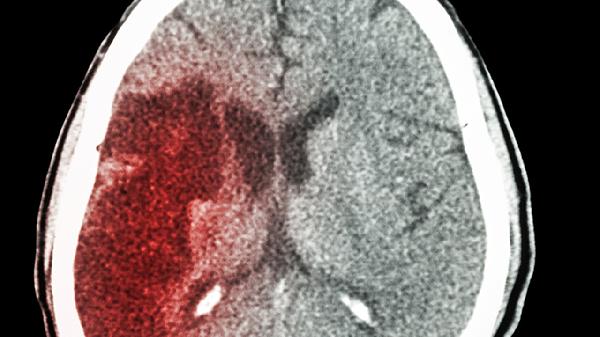

急性脑梗常见症状为突发偏瘫、言语含糊或失语,可能出现面瘫、眩晕及意识障碍。头颅CT早期可无明显异常,MRI弥散加权成像能早期显示缺血灶。高血压、房颤、颈动脉斑块是主要诱因。治疗需在时间窗内静脉注射阿替普酶溶栓,口服阿托伐他汀钙片稳定斑块,配合丁苯酞软胶囊改善脑循环。康复期需进行肢体功能训练和语言康复。